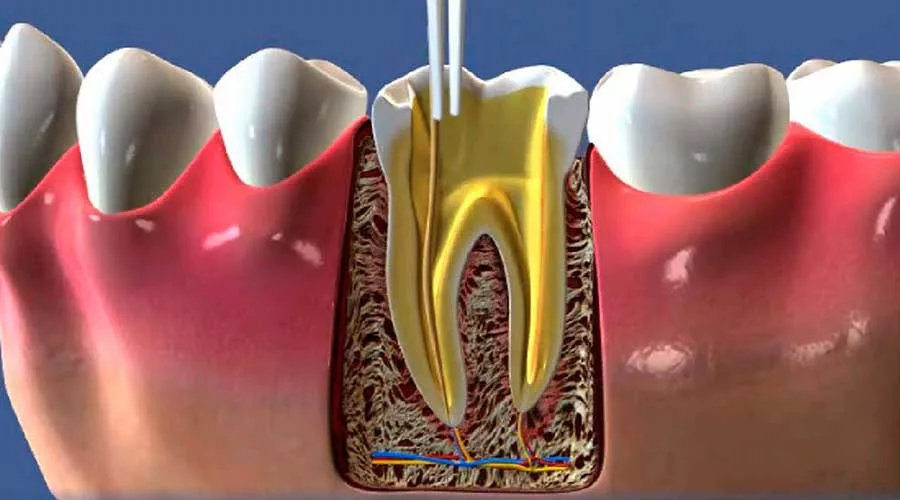

Este procedimento, tecnicamente chamado de endodontia, é o pilar fundamental para salvar dentes comprometidos por cáries profundas ou traumas, proporcionando benefícios que impactam diretamente o bem-estar diário.

A intervenção especializada atua diretamente na causa do problema, removendo o tecido infectado e estabelecendo um ambiente bucal equilibrado e livre de inflamações.

Ao optar pela desinfecção interna em vez da extração, o paciente preserva a funcionalidade mastigatória e o alinhamento da arcada, fundamentando uma saúde bucal estável e duradoura para o cotidiano.

Após a limpeza e desinfecção dos canais radiculares, a saúde sistêmica do paciente melhora significativamente.

Ao cessar o foco infeccioso na boca, evita-se que micro-organismos atinjam a corrente sanguínea, protegendo o coração e outros órgãos, além de restabelecer a estética e a segurança ao sorrir.

Sessão de Endodontia: Remoção da polpa, limpeza minuciosa e selamento com materiais biocompatíveis;